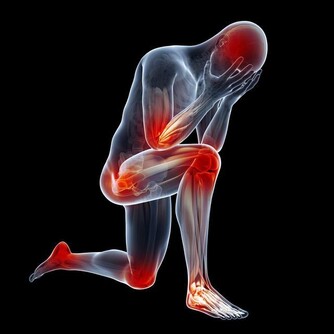

2. 神經因素:

神經內有軸漿流動, 當神經受到壓迫時,

軸漿流動受阻礙, 亦會引起手麻.

到手掌主要有橈神經, 尺神經, 正中神經,

這些神經從頸椎管出發, 穿過關節, 韌帶, 骨纖維管到達手掌末梢,

在任何一個部位, 神經受到壓迫, 均會引起手麻.

3. 大腦因素:

所有神經均來源於大腦, 當腦部出問題.

如中風, 則大腦所支配區會出現麻木, 無力.